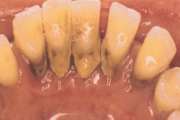

Krooniline parodontiit

Krooniline parodontiit on mikroobide poolt põhjustatud hammaste tugikudede põletik, mille tulemusena tekib progresseeruv alveolaarluu (nähtav röntgenograamil) ja periodontaalligamendi destruktsioon, igemetaskute moodustumine, igeme retsessioon või mõlemad kahjustused kombineeritult. Loe edasi »

- puudulik suuhügieen (5)

- igemepealne hambakivi (5)

- igemealune hambakivi (4)

- igemed veritsevad (19)

- igemed punetavad (21)

- igemed on tursunud/vohavad (17)

- igemepiir on taandunud (3)